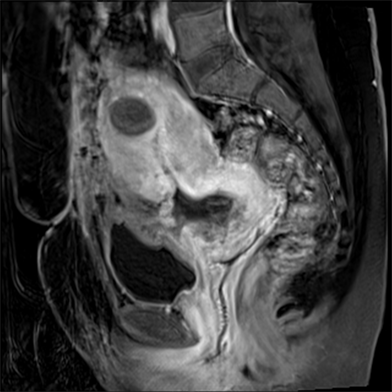

On 16/6/2021, MRI was done without dye and reported a cervical ectopic pregnancy 15 weeks gestation totally present in cervical canal, Figure 3. The placenta was located at the anterior and right lateral aspect of the cervical wall, with marked stretching, thinning of the underlying myometrium and focal interruptions of the myometrial line together with significant contour bulge (suggestive of placenta accreta spectrum, increta subtype), there were markedly increased regional vascularity and blurring of the urinary bladder wall but no evidence of gross intravesical extension. Prominent vascularity is also noted all over the cervical and peri-cervical regions, Figure 4. The main uterine cavity proper showed no sacs and the uterus showed two fibroids, the largest (3 × 3 cm) located at the upper aspect of the anterior uterine wall and having sub-mucosal extension.

Figure 3. T2 weighted MRI image in sagittal plane, showing the 16 weeks fetus sitting peacefully in a markedly distended cervical canal and placenta implanted on the anterior aspect of it. The characteristic hour-glass uterus over-rides the pregnancy, with closed internal os and empty cavity.